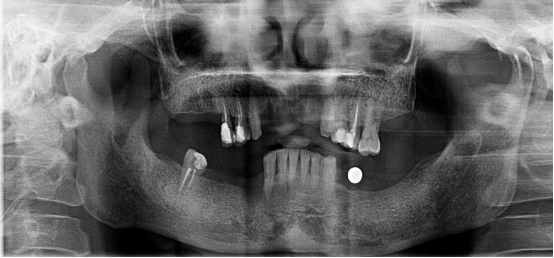

不連續(xù)性牙缺失修復案例

53歲的周女士家住福州晉安,由于患有嚴重的牙周炎導致牙齒沒剩下幾顆了。

“這邊缺一顆,那邊缺幾顆,這咬東西也太不得勁了,有牙齒跟沒牙齒一樣。”周女士深知牙齒缺失的痛苦,但是卻因為經濟的原因一直拖延沒有進行牙齒修復:“做牙齒多貴了,一顆就幾萬塊哪里舍的?!?

錢雖然重要但缺失牙確實痛苦。而近期周女士又湊巧在報紙上看到科爾口腔的“敬業(yè)?!惫婊顒拥南ⅲ活w牙齒可以免費領取4000元的種植牙紅包,優(yōu)惠力度之大前所未有,種植5顆還可以省下幾萬塊。

周女士來院與劉斌元教授進行交流后,劉斌元教授表示:“周女士缺失的牙齒是非連續(xù)性的,因此要種上好幾顆。牙齒缺失千萬不可掉以輕心,長時間缺失牙齒可造成牙槽骨萎縮,還會影響相鄰牙齒健康狀況”